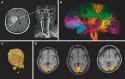

Diffusion MRI has been used worldwide to produce images of brain tissue structure and connectivity, in the normal and diseased brain. Diffusion MRI has revolutionized the management of acute brain ischemia (stroke), saving life of many patients and sparing them significant disabilities. In addition to stroke, diffusion MRI is now widely used for the detection of cancers and metastases (breast, prostate, liver). Another major field of application of diffusion MRI regards the wiring of the brain. Diffusion MRI is now used to map the circuitry of the human brain with incredible accuracy, opening up new lines of inquiry for human neuroscience and for the understanding of brain illnesses or mental disorders. Here, as a pioneer of the field, I provide a personal account on the historical development of these concepts over the last 30 years.